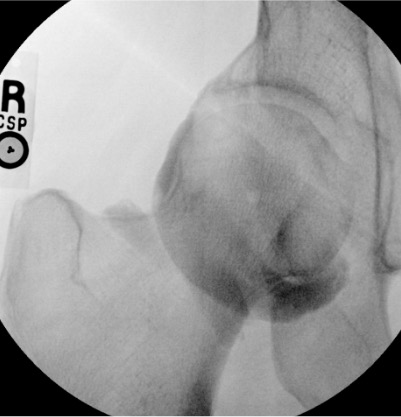

| Hip | 10–20 mL (MR arthro: 12–15 mL) | Fluoroscopy | Anterior approach | Femoral head-neck junction; confirm intra-articular with ring sign — contrast outlines femoral head circumferentially; iliopectineal bursa communicates with joint in ~15% (acceptable) |

Hip

Needle placementPost-injection